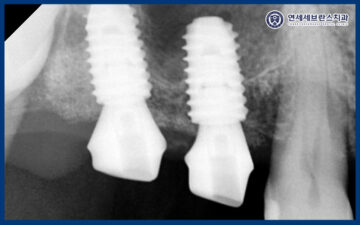

24.11.18

이렇게 잇몸치료가 전체적으로 마무리된 이후에는

본격적인 임플란트 식립을 진행하였습니다.

왼쪽 아래 치아의 경우 발치와 동시에

즉시 임플란트 식립을 시행하였으며,

전반적으로 치조골이 부족한 상태였기 때문에

임플란트의 초기 고정력과

장기적인 안정성을 확보하기 위해

뼈이식을 동반하여 식립을 진행하였습니다.

이를 통해 임플란트가

보다 단단하게 자리 잡을 수 있는

기반을 형성하고, 이후 보철 단계까지

안정적으로 이어질 수 있도록

치료를 계획하였습니다.